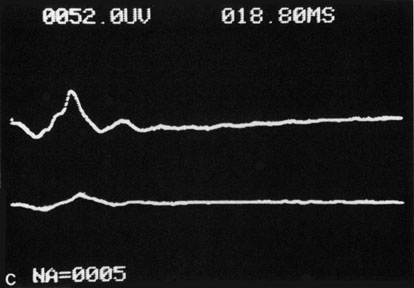

The electroretinogram (ERG) is usually abnormal in central retinal artery obstruction. The b-wave is reduced, indicating a marked abnormality in the circulation of the inner retina.17,18 The a-wave, indicating normal photoreceptor function, is preserved or accentuated. There does not appear to be a good correlation, however, between the extent of b-wave abnormality and the degree of retinal function,3 although Yotsukura and Adachi-Usami420 reported that the b-wave amplitude increased with visual improvement. The photopic negative response (PhNR) shows severe depression in this condition reflecting the significant loss of the ganglion cells and their axons.377 The electrooculogram may be either normal or abnormal. Visual field defects are usually profound but either occasionally a small portion of the temporal peripheral visual field remains or the patient has a large central scotoma.3 The onset of obstruction occurs most often between the hours of midnight and 6 AM, with the second most common period being between 6 AM and noon.2

Hypoperfusion retinopathy is characterized by dot and blot hemorrhages in the midperiphery of the fundus, by venous tortuosity and engorgement, by microaneurysms, and by the occasional sludging of blood within the veins. Fluorescein angiography may show areas of capillary nonperfusion; it may also show microaneurysms in the midperiphery and slow arm to retina or arteriovenous transit time (Fig. 9A and 9B).174 The condition does not usually affect the posterior pole, and patients typically have normal visual acuity, although an occasional patient may have macular edema.174 The entire periphery of the eye is usually affected, although there may be more hemorrhages in one quadrant than another. Patients occasionally experience ocular discomfort or eye pain despite normal intraocular pressure. Reduction of the ophthalmic arterial pressure is a pathognomonic feature. Disc edema and disc collaterals are generally not present. The electroretinogram shows abnormalities in both the a- and b-waves (see Fig. 9C).

Fig. 9. Intravenous fluorescein angiogram of a patient with hypotensive or hypoperfusion retinopathy. A: There is a marked delay in the choroidal and retinal filling. B: In the recirculation of the angiogram, there is a characteristic staining of both arteries and veins. C: Electroretinogram shows normal a- and b-waves in the normal right eye (upper tracing) and marked redirection of the a- and b-waves in the affected left eye (lower tracing).